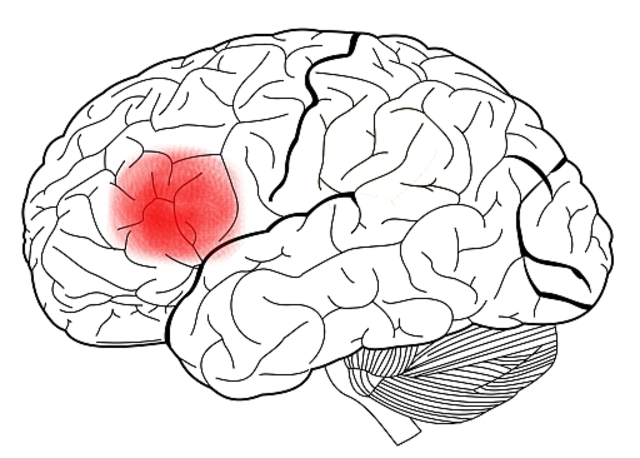

• Paul Broca

Paul Broca

Descubrió el centro del habla en el cerebro (área Broca o tercera circunvolución frontal izquierda) e hizo un mapeo de este.